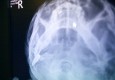

Liječnici iz kineskoga grada Chongqinga izvadili su ženi metak iz glave 42 godine nakon što je ondje dospio, objavili su u petak mjesni mediji. Kineskinju He Wenying (65) metak je slučajno pogodio 1967. godine u okršaju suprotstavljenih frakcija Crvene garde na početku kineske Kulturne…